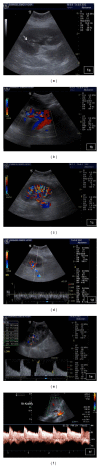

Renal transplantation is the treatment of choice for managing patients with end-stage kidney disease. Being submitted to a very serious surgical procedure, renal transplant recipients can only benefit from follow-up imaging and monitoring strategies. Ultrasound is considered as the principal imaging test in the evaluation of renal transplants. It is an easily applied bedside examination that can detect possible complications and guide further imaging or intervention. In this imaging review, we present essential information regarding the sonographic features of healthy renal transplants, detailing the surgical technique and how it affects the sonoanatomy. We focus on various complications that occur following renal transplantation and their sonographic features by reviewing pertinent literature sources and our own extensive imaging archives.